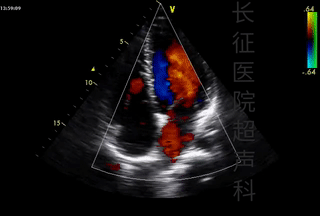

可以观察心脏各个“房间”的大小、形态是否正常,“门窗”、“墙壁”是否完整,功能是否正常;在此基础上添加彩色多普勒和频谱多普勒,可以观察心脏的血流是否正常,有无异常分流,并测量血流速度,评估心脏的血流动力学参数。

心尖四腔心切面

彩色多普勒血流成像